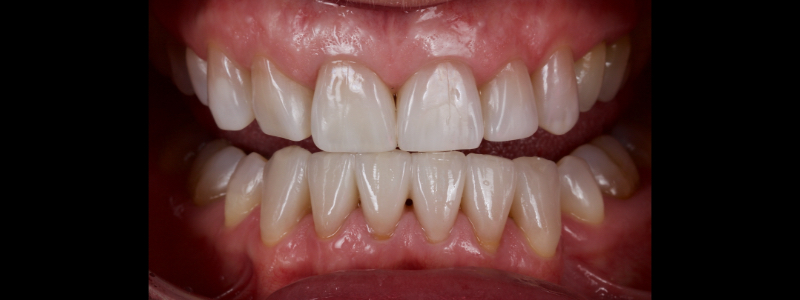

To illustrate this protocol, we will explore the case of a 55-year-old female patient — a dentist — with esthetic and functional concerns as well as moderate to advanced tooth surface loss (TSL).

The anterior teeth had lost around 25% of the coronal structure, and dentin was exposed (Figs. 1–3). The patient requested a minimally invasive solution.

After deprogramming with a splint and occlusal equilibration, the anterior teeth were restored with direct composite resin using a minimal prep approach (Figs. 4 and 5). The occlusal scheme was idealized (Fig. 6).